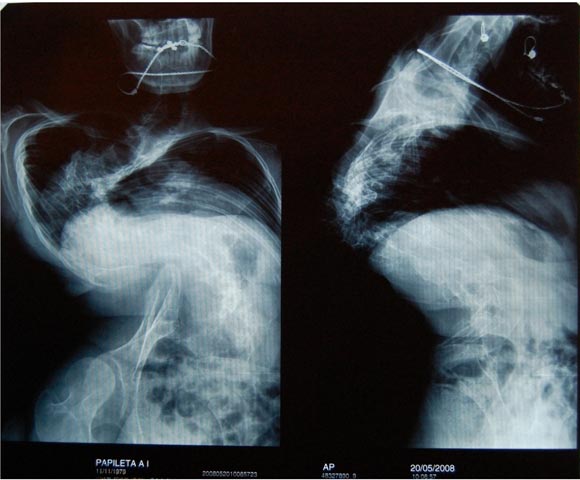

Папилета Анна 28.03.1979 года рождения

Диагноз: Врожденный кифосколиоз 4 ст..

У меня, врожденный правосторонний S образный кифосколиоз четвертой степени, в тяжелой форме, более 160 градусов искривления позвоночника. Врожденный вывих правого тазобедренного сустава, косой таз. Из-за сильного перекоса таза, одна нога значительно короче другой. И из-за всего этого серьезно сдавлены все органы и нарушается кровоснабжение ног, ухудшено кровоснабжение головы.

Все мотивировали отказ тем, что у меня очень сложный случай, да еще и уже однажды оперированный, а это все усложняет. Объясняют, что после операции, на позвоночнике сформировался костный блок, и разделять его теми методами, что доступны в наших институтах, очень опасно. Высока вероятность парализации.